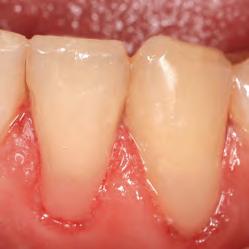

Ultradent Universal Dentin Sealant is a biocompatible, nonpolymerizable, high-molecular-weight resin in a volatile organic solvent.

Coat sensitive roots with Ultradent Universal Dentin Sealant to seal tubules and reduce discomfort after root planing or scaling.